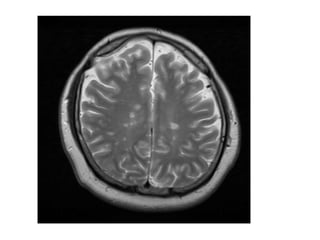

MRI Brain T2WI

Relapsing-Remitting MS

• Revised McDonald criteria

• MRI: Periventricular, brainstem, juxtacortical

prominent T2, often Gad enhancing lesions, T1

hypointense (black holes)